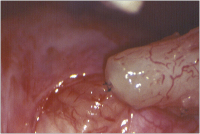

Refertilisierung und ICSI bei obstruktiver Azoospermie

Journal für Reproduktionsmedizin und Endokrinologie - Journal of Reproductive Medicine and Endocrinology 2010; 7 (5): 408-412 Volltext (PDF) Summary Praxisrelevanz Abbildungen